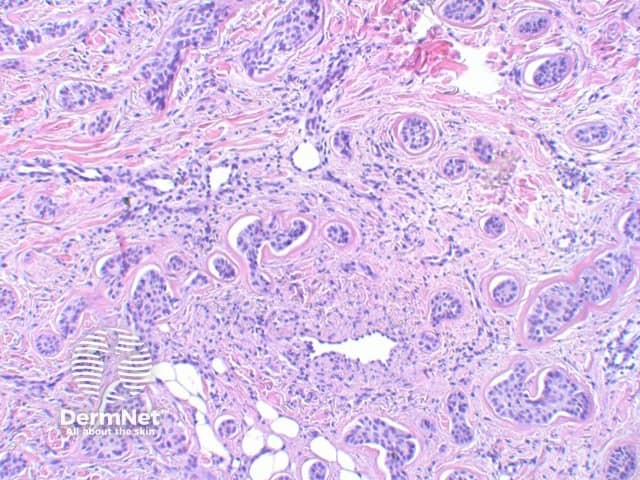

The key feature of basal cell carcinoma at low power magnification is of a basaloid epithelial tumour arising from the epidermis (figure 1). The basaloid epithelium typically forms a palisade with a cleft forming from the adjacent tumour stroma (figure 2). Centrally the nuclei become crowded with scattered mitotic figures and necrotic bodies evident (figure 3). A useful distinguishing feature from other basaloid cutaneous tumours is the presence of a mucinous stroma (figure 4). Some tumours may also show foci of regression, seen as areas of eosinophilic stroma with lack of basaloid nests.

Figure 2

Figure 3